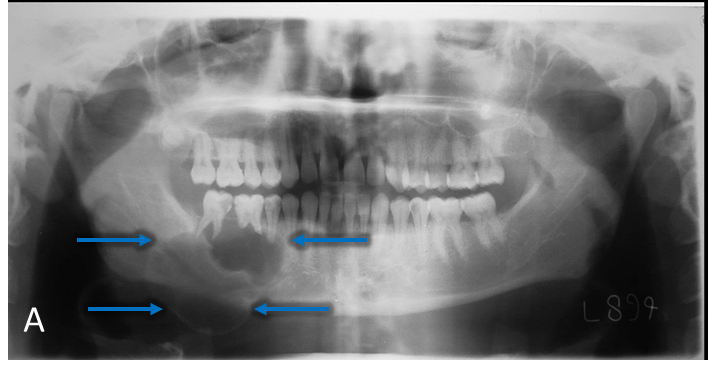

A 30-year-old male patient presented with the chief complaint of swelling in the right second molar area for past 7 months (Figure A, blue arrow).

Panoramic radiograph (A) demonstrates a multilocular, well-defined, partially corticated, radiolucent lesion in the mandibular right posterior region (blue arrow). Lesion extends anterior-posteriorly from #28 to #31 and occupies the superior two-thirds of the mandibular body. Lesion is causing interruption of the alveolar crest and external root resorption of #29-31. Mandibular canal is mildly displaced near the anterior aspect of the lesion. Lateral occlusal radiograph (B) demonstrates a multilocular radiolucent lesion in the premolar-molar region (green arrow). Lesion is causing expansion and interruption of the buccal and lingual cortices with lingual displacement of #31. Axial CBCT (C) demonstrates expansion and interruption of the buccal and lingual cortical plates (red arrows). Coronal CBCT (D) demonstrates expansion and interruption of the alveolar crest and the buccal and lingual mandibular cortices (yellow arrows). CBCT 3D Reconstruction (E) demonstrates locular internal borders (pink arrow).